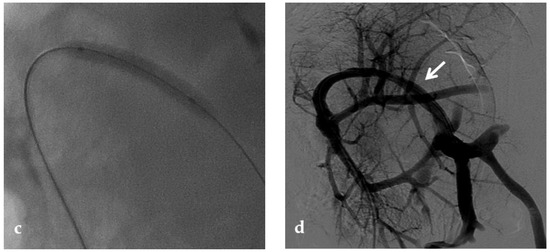

Percutaneous transluminal angioplasty (PTA) relies on the dilatation of the occluded portal tract with balloon catheters during percutaneous transhepatic portography and it is highly effective for PVT [69] (Figure 9). In some cases of late-onset PVT, the fibrosis of the thrombosed segment may be an important determinant of recurrence and PTA may require additional metallic stent placement [8].

Figure 9.

Anteroposterior view of a percutaneous transhepatic portography imaging series performed for chronic complete portal vein thrombosis with cavernous transformation in an 11-year-old boy with a history of gastrointestinal bleeding and portal hypertension 10 years after deceased-donor orthotopic liver transplantation (split II–III) for biliary atresia. (a) Portography image shows a regular representation of the segment 3 portal branch, while the segment 2 portal branch has a peripheral defect of opacification due to flow reversal, resulting from portal cavernoma and extrahepatic capsular feeding from gastric vessels (black arrow). Complete occlusion of the extrahepatic portal vein at the hepatic hilum (white arrow) is demonstrated. (b) Portography image shows the opacification of a very tiny vascular structure (arrow) which represents what remains of the thrombosed extrahepatic portal trunk. (c) Fluoroscopy image shows angioplasty with a non-compliant 8-mm balloon catheter performed on a stiff guidewire which was advanced across the obstructed tract. (d) Control portography shows a re-expanded extrahepatic portal vein (arrow) with normal spleno-portal opacification. Portal vein thrombosis recurred one year after treatment and required repeated angioplasty and metal stenting (shown in the next figure).